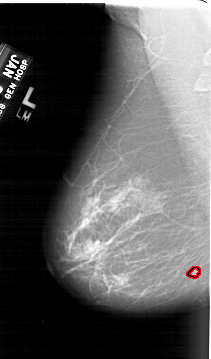

A_1687_1.LEFT_MLO

LEFT_MLO LINES 6451 PIXELS_PER_LINE 3796 BITS_PER_PIXEL 12 RESOLUTION 43.5 OVERLAY

FILE: A_1687_1.LEFT_MLO.OVERLAY

TOTAL_ABNORMALITIES 1

ABNORMALITY 1

LESION_TYPE MASS SHAPE LOBULATED MARGINS ILL_DEFINED

ASSESSMENT 4

SUBTLETY 4

PATHOLOGY BENIGN

TOTAL_OUTLINES 1